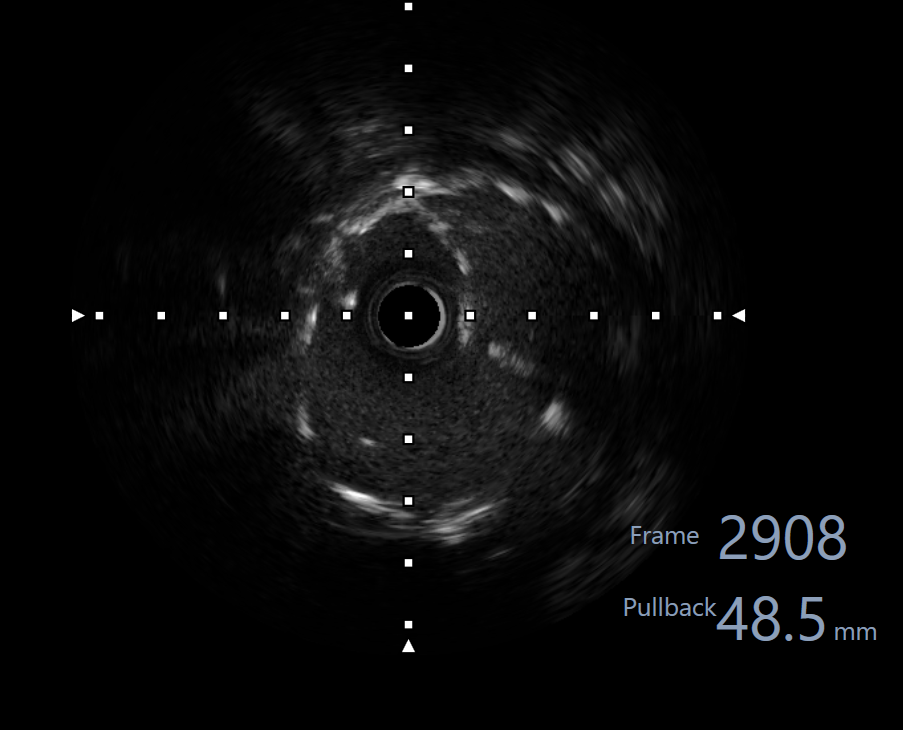

Right femoral artery punctured approach by 7Fr femoral sheath. Coronary guide catheter EBU 3.5 was used to engage left coronary artery. Percutaneous Coronary Intervention (PCI) to bifurcation Medina 1,1,1 using T and small protrusion (TAP) technique. LAD and LCX wired with workhorse wire . Mid LAD predilated with Semi-compliant (SC)2.5mm balloon and proximal LAD predilated with non-compliance (NC) 3.5mmballoon. Intravascular Ultrasound ( IVUS) was performed to measure the vessel size, lesion length and plaque morphology. Mid LAD stented with 3.5x23 mm drug eluting stent (DES). LM until proximal LAD stented with 4x33mm DES . Proximal optimization therapy (POT) at LM with NC balloon 5x8mm. Proximal LAD post dilated with NC balloon 4x20mm and mid LAD post dilated with NC balloon 3.5x15mm. LCX rewired with workhorse wire. Ostial LCX predilated with NC balloon 3.5x15mm and stented with 3.5x23mm DES subsequently post dilated with NC balloon 3.75x20mm. Final kissing balloon inflation was done at ostial LAD using NC balloon 4.0 and ostial LCX using NC balloon 3.75. Final IVUS noted double barrel sign at LM stent and confirmed with stent enhancement likely due to abluminal side branch wiring. Final POT to LM with NC balloon 5x8mm. Final IVUS showed good stent expansion and opposition with no dissection.

Case Summary

This case highlighted the importance of using IVUS in doing PCI. Importance of intravascular imaging in PCI was highlighted in recent 2024ESC guidelines and it’s class 1 evidence. Besides assessing the lesion length, diameter and plaque morphology, it can ensure good stent opposition and expansion. This is crucial to prevent complication during bifurcation stenting.